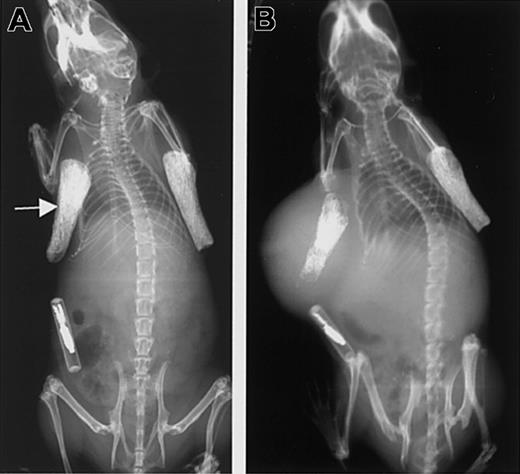

Because a high concentration of soluble syndecan-1 ectodomain in the serum is an indicator of poor prognosis in patients with myeloma,10,11 we compared the in vivo growth and dissemination of ARH-77 cells that express either soluble syndecan-1 ectodomain or cell surface syndecan-1. An additional control included neo-transfected ARH-77 cells that lack syndecan-1 expression. These experiments were performed by using the SCID-hu model in which a fragment of human bone is implanted subcutaneously in each side of a SCID mouse. Although these experiments are very labor intensive, they provide an excellent model for studying the experimental growth of human tumors within a human marrow microenvironment. Several weeks after implantation of the bone, tumor cells were injected directly into the bone on the left side (primary tumor).20 At the conclusion of the experiment, the bone on the right side was analyzed for the presence of tumor cells as a measure of tumor dissemination (secondary tumor).15 Although injected directly into the bone, as the tumors enlarge, they often grow outside of the bone and surround the bone implant (Figure 5).

Growth of tumor in the SCID-hu mouse.

(A) X-ray showing the 2 bone implants just prior to injection of tumor cells into the left bone (arrow). (B) The same animal as in the left panel is shown 8 weeks after injection of cells expressing soluble syndecan-1 ectodomain. Note the injected bone shows evidence of osteolysis and that the primary tumor has enlarged and surrounds the bone.